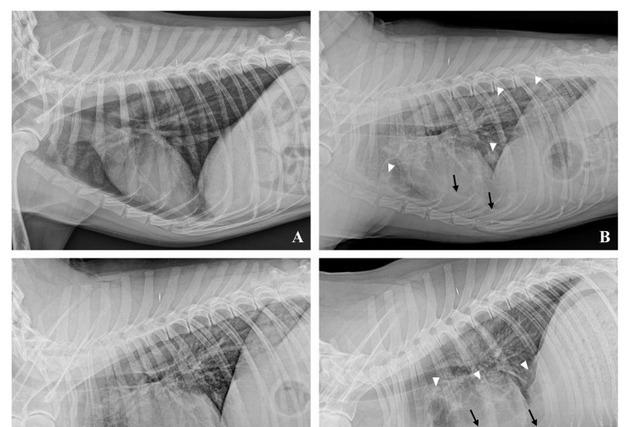

반려동물 골육종의 폐 전이 관리를 위한 '삼중 병용 항암 요법'의 임상적 효용성을 입증하는 연구 결과가 공개됐다. FM동물메디컬센터와 대구한의대 반려동물산업학과 연구팀이 공동 진행한 이 연구 결과는 국제 학술지인 '아이리시 베테리너리 저널(Irish Veterinary Journal)'에 발표됐다.16일 벳아너스 회원 병원인 FM동물메디컬센터(대표원장 곽지훈 외)에 따르면 골육종은 강아지에게 치명적인 악성 종양이다. 이미 육안상 폐 전이가 진행